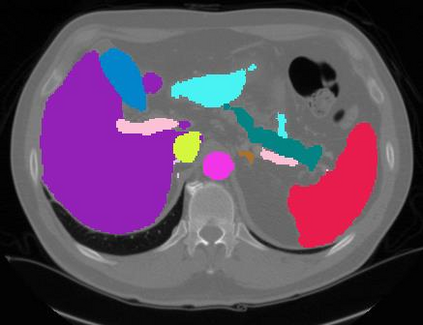

Vision transformers, with their ability to more efficiently model long-range context, have demonstrated impressive accuracy gains in several computer vision and medical image analysis tasks including segmentation. However, such methods need large labeled datasets for training, which is hard to obtain for medical image analysis. Self-supervised learning (SSL) has demonstrated success in medical image segmentation using convolutional networks. In this work, we developed a \underline{s}elf-distillation learning with \underline{m}asked \underline{i}mage modeling method to perform SSL for vision \underline{t}ransformers (SMIT) applied to 3D multi-organ segmentation from CT and MRI. Our contribution is a dense pixel-wise regression within masked patches called masked image prediction, which we combined with masked patch token distillation as pretext task to pre-train vision transformers. We show our approach is more accurate and requires fewer fine tuning datasets than other pretext tasks. Unlike prior medical image methods, which typically used image sets arising from disease sites and imaging modalities corresponding to the target tasks, we used 3,643 CT scans (602,708 images) arising from head and neck, lung, and kidney cancers as well as COVID-19 for pre-training and applied it to abdominal organs segmentation from MRI pancreatic cancer patients as well as publicly available 13 different abdominal organs segmentation from CT. Our method showed clear accuracy improvement (average DSC of 0.875 from MRI and 0.878 from CT) with reduced requirement for fine-tuning datasets over commonly used pretext tasks. Extensive comparisons against multiple current SSL methods were done. Code will be made available upon acceptance for publication.